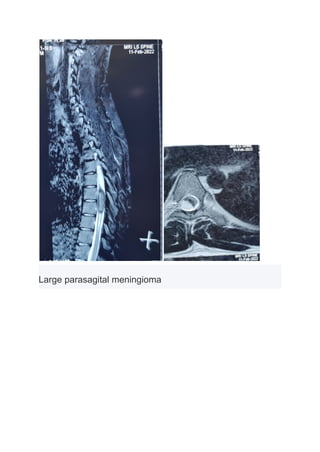

Spinal Meningioma

Large parasagital meningioma